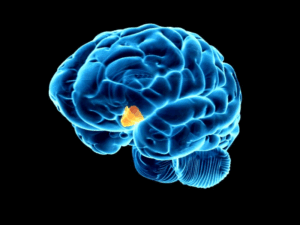

Durante la menopausia, los niveles de estrógeno —una de nuestras hormonas principales— comienzan a bajar. Ese cambio afecta una zona del cerebro llamada hipotálamo, que es como nuestro “termostato interno”. Cuando ese termostato se desajusta, cualquier pequeña variación puede hacer que el cuerpo entre en alerta, como si tuviéramos fiebre.